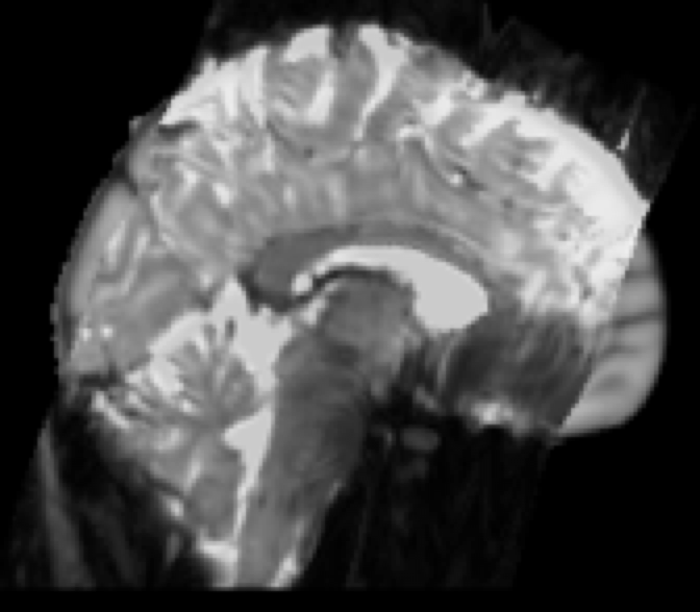

Example result: Partial FOV EPI (functional) resampled to standard space

Partial FOV to Standard Space Example